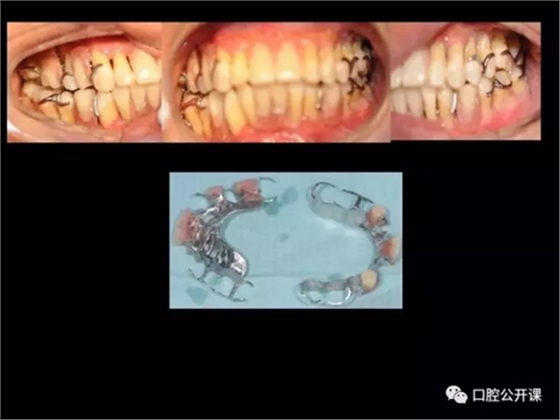

楊淑銀醫(yī)師用他的一例侵襲性牙周炎五年臨床病例追蹤來(lái)縮影一個(gè)青年牙周醫(yī)師的成長(zhǎng)之路,帶我們一起探索看似平凡枯燥的牙周基礎(chǔ)治療到底有怎樣的重要性?